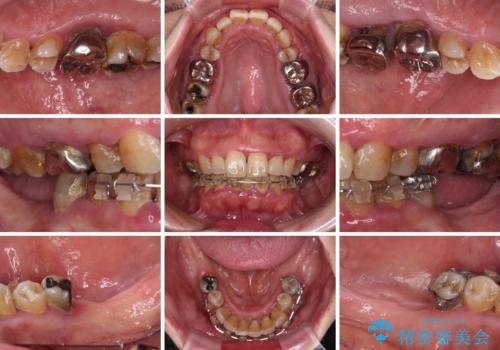

- インプラント治療を前提に下顎の部分矯正を始めたものの、そのまま長い間放置しているとのことで来院された患者様です。

全体的に歯肉が腫れており、歯周病により抜歯をしなければならない歯がある状態でした。

矯正治療を仕上げ、必要に応じて歯周外科処置を行い、適宜インプラントを埋入しながら咬み合わせを回復させていくこととしました。

最終的に奥歯はオールセラミッククラウンによる補綴治療を行うこととしました。

治療前は磨き残しが多く見られ、全体的に歯肉が腫れている状態でしたが、抜歯の必要な歯を抜いたことで口腔内の環境が改善され、磨き残しも少なくなってきました。